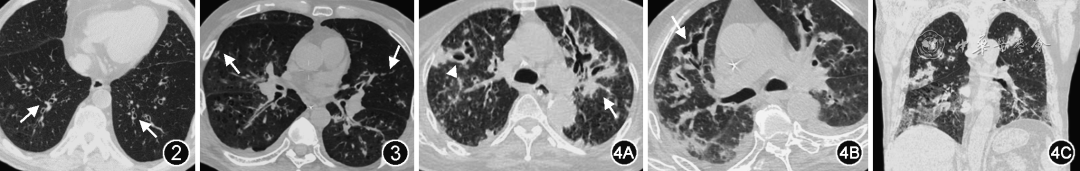

慢阻肺伴IPA的影像学表现往往缺乏晕轮征、新月征等血管侵袭性肺曲霉病的典型表现,而更多表现为气道侵袭性肺曲霉病。在气管支气管炎期,X线胸片检查通常无异常发现,或仅表现为肺门周围的“渗出”改变。胸部CT可显示气管或支气管管壁增厚,伴有管腔狭窄;支气管管壁增厚以大气道为著,通常为多叶段受累,偶见局限的叶段受累;肺实质可以不受累,或仅有少量的磨玻璃或实性小叶核心结节(图2)。薄层胸部CT扫描有助于观察支气管管壁增厚情况。值得特别关注的是患者常常出现与影像学改变不匹配的呼吸困难。

图片

图2  气道侵袭性肺曲霉病支气管炎期患者胸部CT典型表现。患者男,84岁,诊断慢阻肺20余年,受凉后喘息加重入院。胸部CT显示双下肺支气管管壁显著增厚(白箭头),临近肺实质内可见少量小叶核心结节和小叶中心型肺气肿改变

图3  气道侵袭性肺曲霉病支气管肺炎期患者胸部CT典型表现。患者男,74岁,诊断慢阻肺10余年,受凉后发热伴痰中带血。胸部CT显示支气管管壁弥漫显著增厚,周围肺实质内可见小叶核心结节,部分融合成小片状实变(白箭头)。双肺内可见小叶中心型肺气肿

图4  气道侵袭性肺曲霉病坏死性支气管肺炎期患者胸部CT典型表现。患者男,84岁,诊断慢阻肺10余年,淋巴瘤化疗后。胸部CT显示双肺支气管管壁弥漫增厚,支气管管壁可见不规则扩张,支气管周围可见实变(白箭头),右肺上叶空洞形成(白三角),空洞内可见丝状分隔(图4A、4B),冠状重建图像显示双上肺小叶中心型肺气肿改变(图4C)

支气管肺炎期可见在增厚的支气管周围出现斑片状致密实变或结节,病灶边界模糊,其内可见支气管气相,周围可见小叶核心结节和/或“树芽征”(图3)

在坏死性支气管肺炎期,实变和结节病灶内形成空洞,空洞早期为厚壁不规则空洞,其内可见分隔,可快速进展为薄壁空腔,腔内可见分隔或网状线样结构;支气管管壁增厚可减轻,可出现不规则的支气管扩张改变,扩张的支气管与空腔延续或相通(图4)